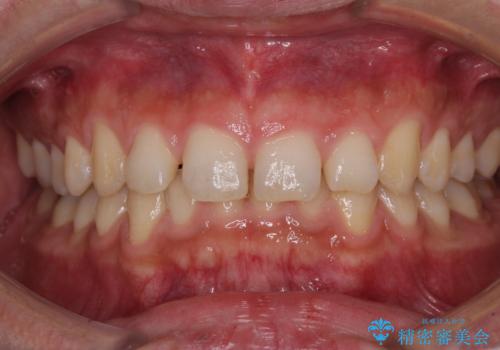

下の歯のがたつき 上より気になる

口元大事です! 見違える矯正!! 乱ぐい歯もあきらめないでください。